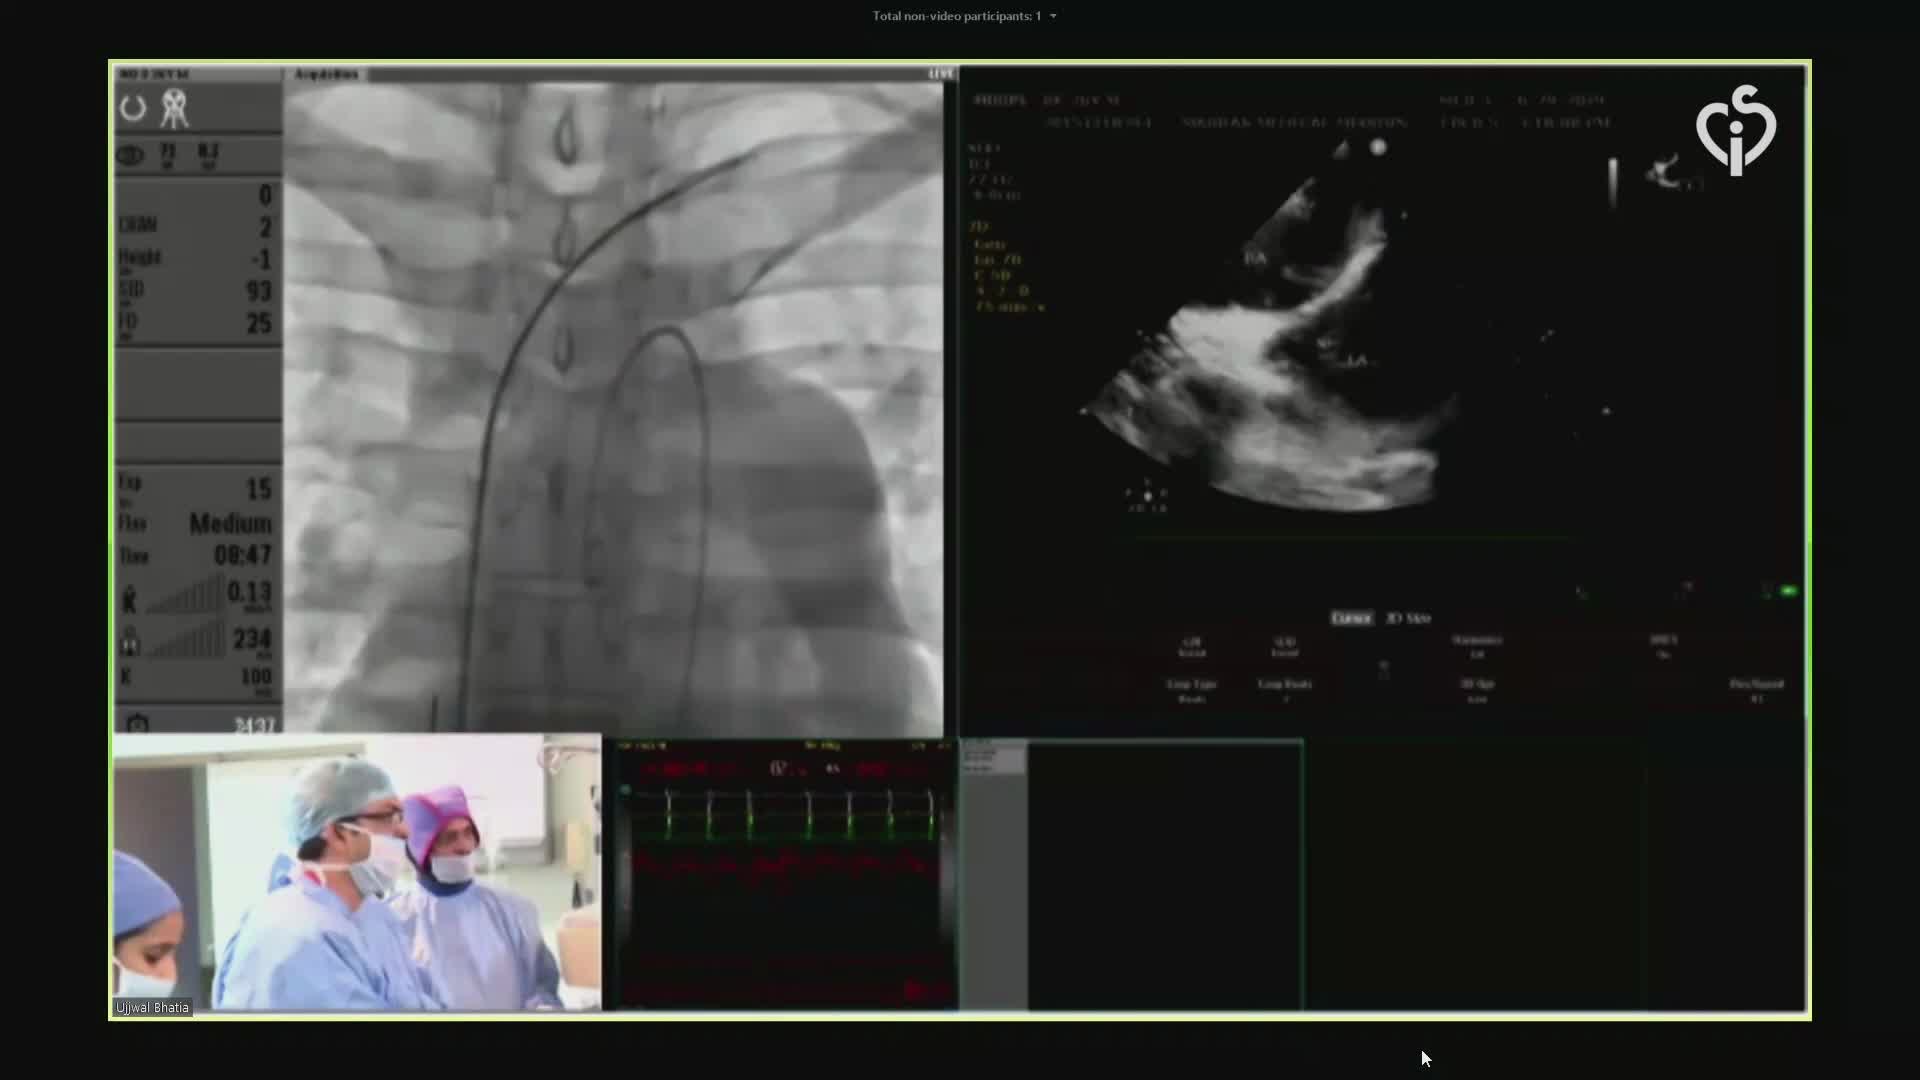

CSI CATHLAB LIVE - INTER-ATRIAL SHUNT FOR DECOMPRESSION OF THE LEFT ATRIUM IN A PATIENT WITH VERY SEVERE HEART FAILURE WITH THE AFR DEVICE